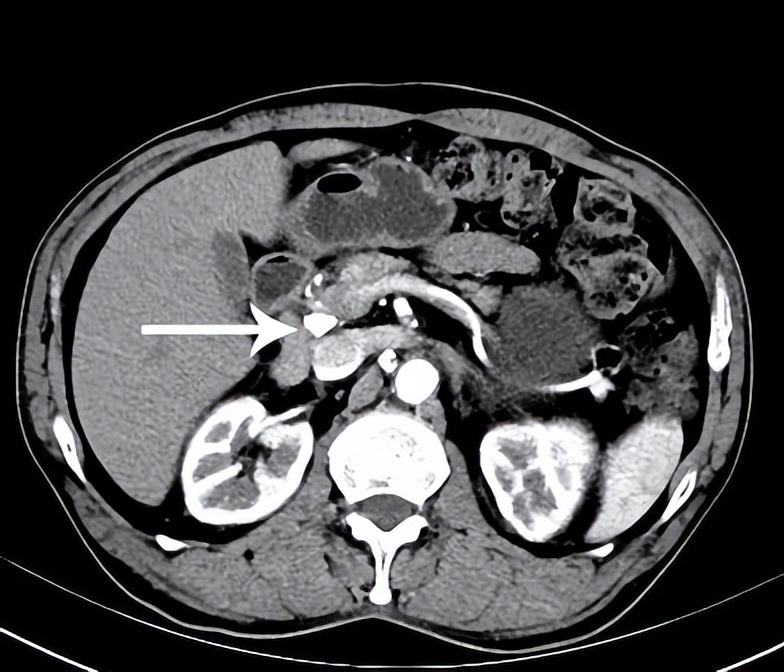

术后半年复查,淋巴结完全消失,仅见粒子聚集影。